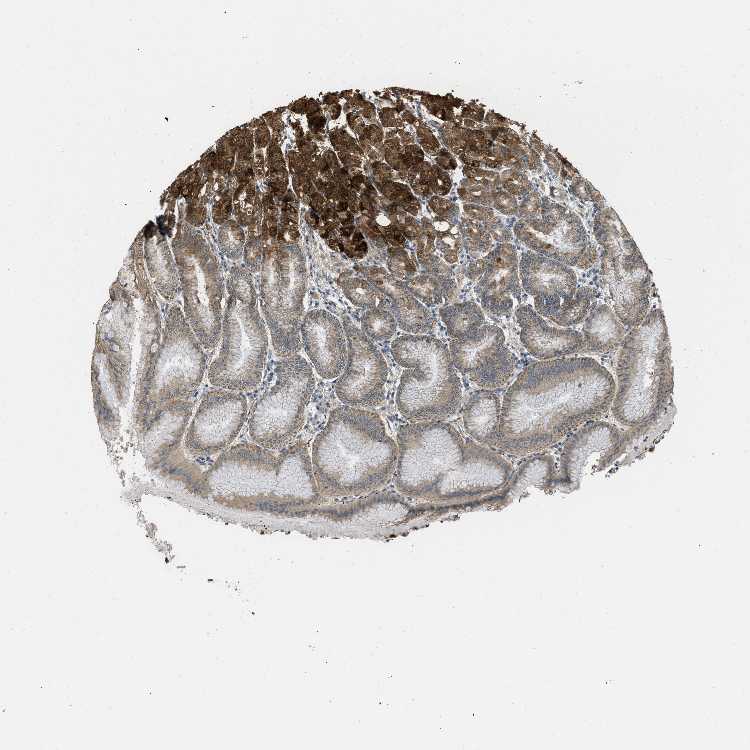

TISSUE PRIMARY DATA STOMACH Show tissue menu

STOMACH 1 - Antibody stainingi

Antibody staining in the annotated cell types in the current human tissue is reported as not detected, low, medium, or high, based on conventional immunohistochemistry profiling in selected tissues. This score is based on the combination of the staining intensity and fraction of stained cells.

Each image is clickable and will lead to virtual microscopy that enables deeper exploration of all samples and also displays staining intensity scores, fraction scores and subcellular localization as well as patient and tissue information for each sample.

Antibody HPA014589Antibody HPA048020Antibody CAB017156

Glandular cells MediumHighMedium